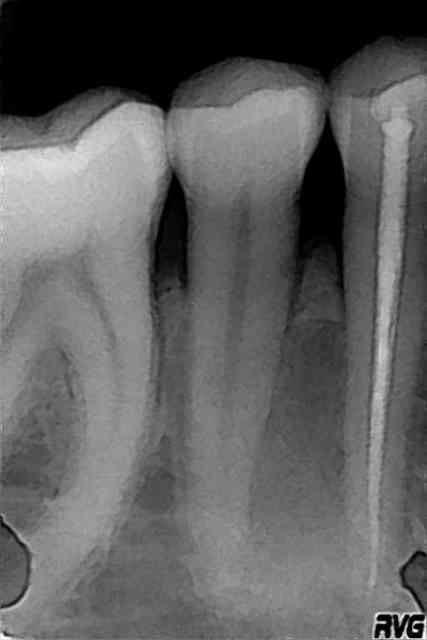

Kyste dentigère.

Radio post op .